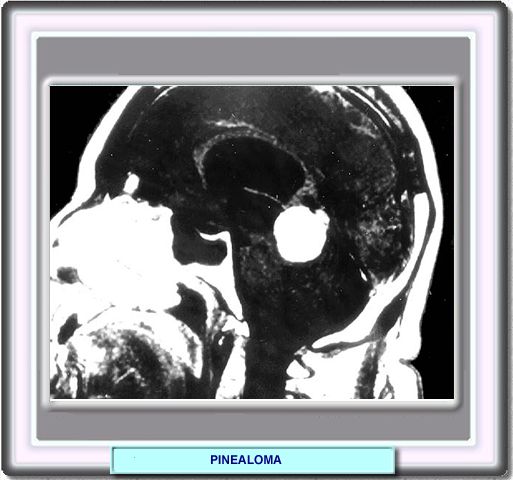

PINEALOMA

Los síntomas y signos neurológicos se deben a un hidrocéfalo obstructivo y afectación del tracto ocular. Los síntomas más importantes son cefaleas, naúseas y vómitos, letargia y diplopía.

La prognosis de estos tumores depende de su histología y del tamaño en el momentpo del diagnóstico. Los pacientes con teratomas maduros responden mejor a la cirugía, mientras que los germinomas son tratados mejor mediante radioterapia.